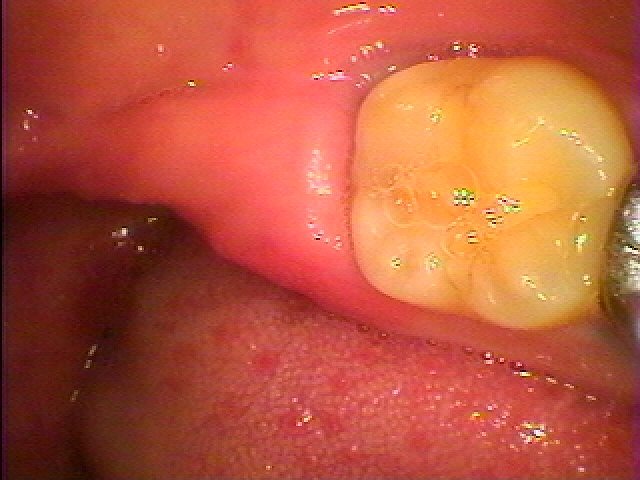

ブログ一覧|広島市安佐南区の歯科医院 ブログ一覧 トップ ブログ一覧 お知らせ スタッフブログ ブログ一覧 2018/05/01 親不知の水平埋伏。 抜歯希望 2018/05/01 転出による歯周病の悪化 2018/05/01 親不知の難抜歯。 こういった歯は頑張って抜くしかないです。 2018/05/01 親不知の抜歯では根が湾曲して分割が必要な下顎の親不知が難抜歯となりやすいです。 2018/05/01 親不知の完全水平埋伏歯抜歯。 皮質骨と癒着している場合もあります。 2018/05/01 親不知の抜歯では根が湾曲して分割が必要な下顎の親不知が難抜歯となりやすいです。 2018/05/01 親不知の水平埋伏。 抜歯希望 2018/05/01 親不知の抜歯では根が湾曲して分割が必要な下顎の親不知が難抜歯となりやすいです。 << 1 2 3 4 5 … 651 652 653 654 655 … 870 871 872 873 874 >> Web診療予約 初めての方へ 選ばれ続ける理由 院内設備について 歯が痛いしみる一般歯科 歯がぐらぐらする歯周病 健康な歯を保ちたい予防歯科 子供の虫歯予防をしたい小児歯科 銀歯をセラミックに審美歯科 白い歯を目指しませんか?ホワイトニング 矯正専門医がいるので安心矯正歯科 抜けた歯を補いたいインプラント・入れ歯 医院案内 スタッフ紹介 メリィハウス歯科クリニックオフィシャルホームページ ラベンダー歯科クリニックオフィシャルホームページ お知らせ・ブログ ホーム 診療科目 一般歯科 歯周病治療 予防治療 小児歯科 審美治療 ホワイトニング 矯正歯科 入れ歯・インプラント マウスピース矯正 初めての方へ 院長・スタッフ 設備紹介 医院案内・アクセス メニューを閉じる